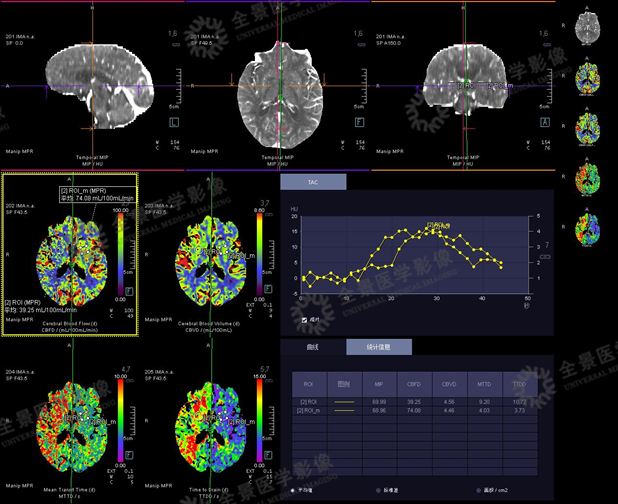

13岁男性患者,因头痛、头晕就诊。

CT平扫示:右枕叶散在钙化灶。

头颅灌注示:右枕叶异常灌注,CBF较左侧降低,MTT、TTD时间延长。

利用灌注的原始数据评估脑血管情况

CTA未见明显异常。

一站式灌注血管成像示:脑动脉未见明显异常。

脑静脉成像可见右侧乙状窦、岩窦较左侧管径增宽,临近右枕叶脉络从静脉血管丰富。

临床诊断为:右枕叶颜面血管瘤综合征(Sturge-Weber综合征)